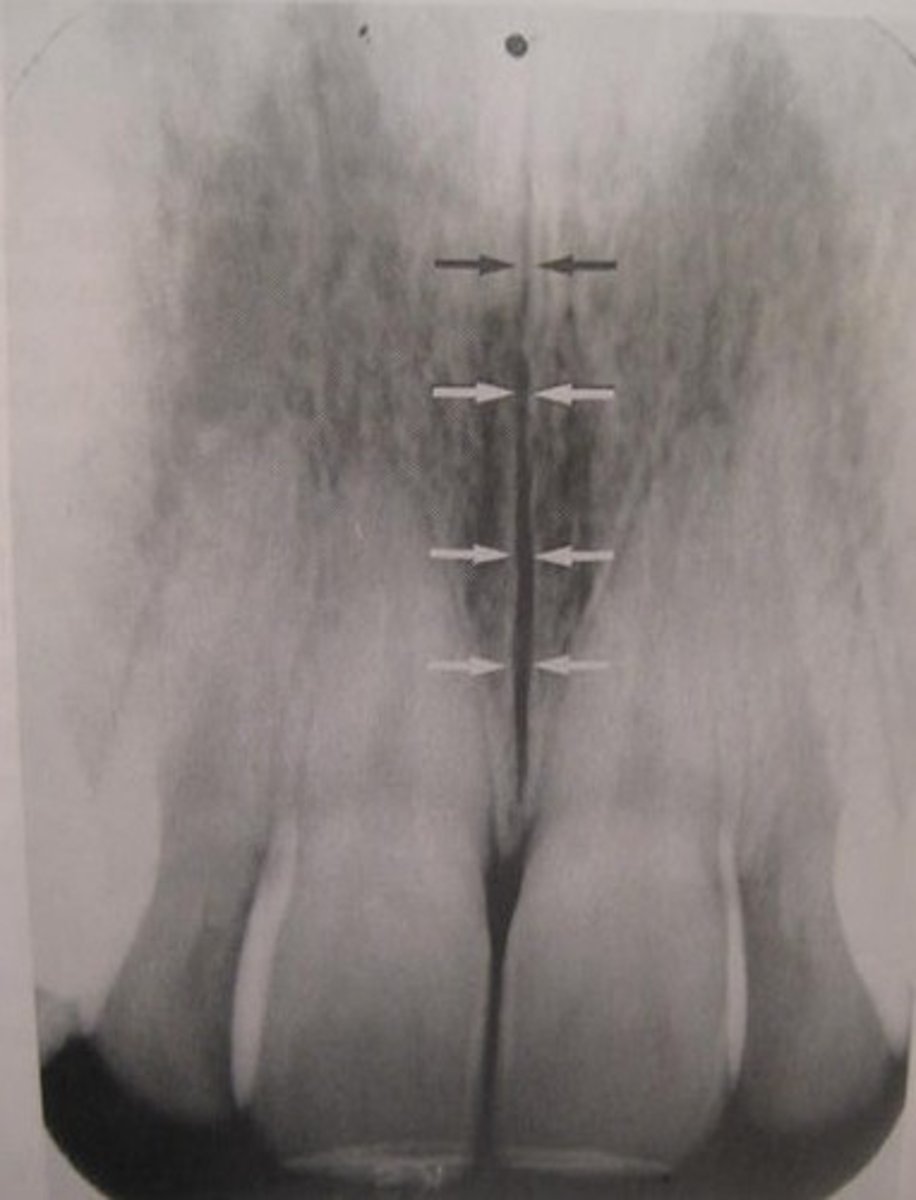

median suture

"crack" between roots of maxillary central incisors

area of incomplete fusion

radiolucent

incisive foramen

hole in the bone of the maxilla and between roots of incisors